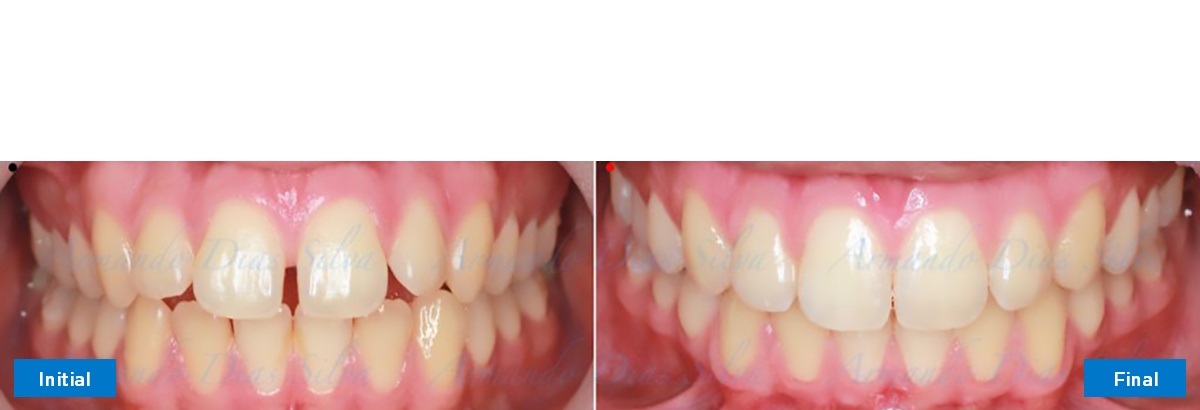

Clase II, Div. 1: Protrusión del incisivo central y espacios anteriores (SureSmile® Aligners)

Principal queja del paciente: Protrusión del incisivo central y mordida abierta. El paciente rechaza la expansión del arco palatino (MARPE) y las extracciones.

Este paciente adolescente presenta molares de Clase II y no le gusta su mordida abierta ni lo protrusivos que son sus dientes frontales. Por sus fotografías faciales, parece que su mandíbula es retrognática o le falta volumen en la barbilla. El historial del paciente también indica que existe un problema funcional al no haber guía de los incisivos.

• Diastema

• Incisivos superiores e inferiores proclinados

• Retruir los incisivos superiores

• Retroclinar los incisivos inferiores

Se logran todos los objetivos principales:

• Molares de clase I logrados con distalización y sin elásticos

• Sin expansión maxilar, respetando la envoltura periodontal

• Incisivos inferiores retroinclinados, que mejoran la estabilidad a largo plazo

Retención: Arco superior retenido con retenedor transparente. Arco inferior retenido con retenedor lingual unido de canino a canino.